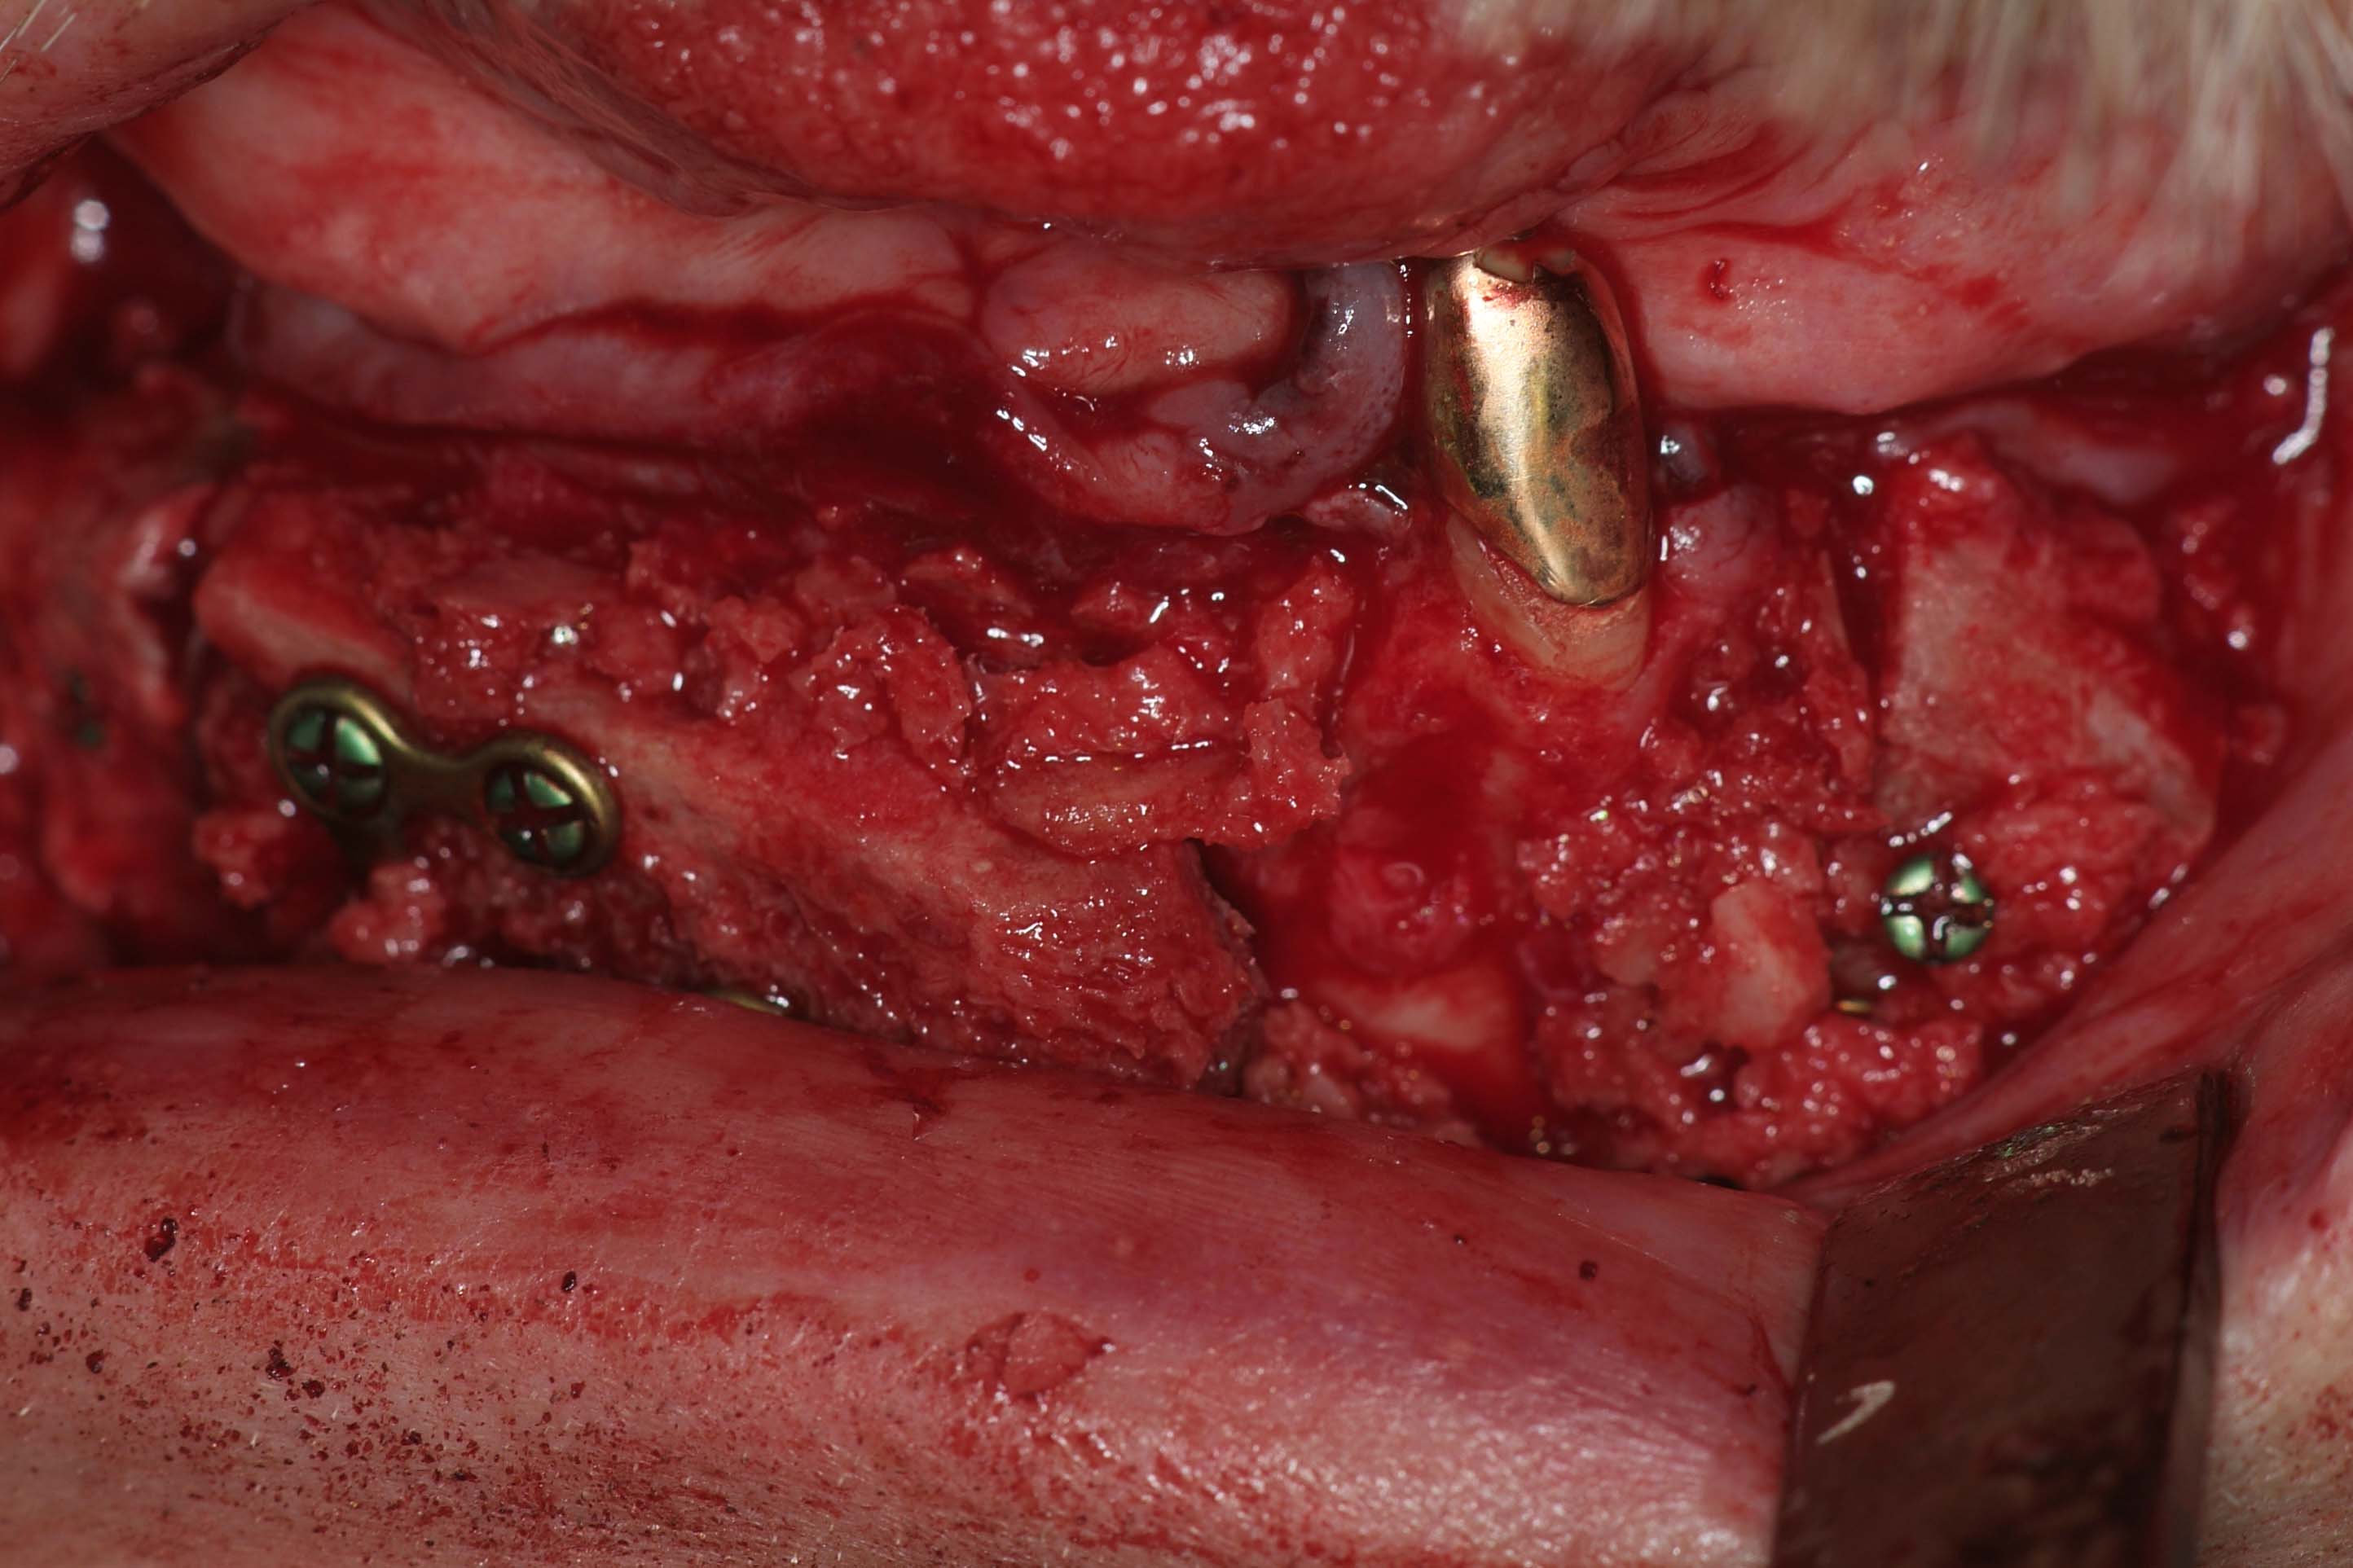

Für derart komplexe Fälle ist das interdisziplinäre Zentrum für Zahnärztliche Implantologie der Ansprechpartner: Der Patient wird in einer interdisziplinären Sprechstunde vorgestellt und die Planung des Patienten in dem interdisziplinär geleiteten Implanatboard erstellt. Anschließend erfolgt der Knochenaufbau in ITN. Dabei werden die angelagerten Knochenstücke über sogenannte Osteosyntheseplatten in den Bereichen fixiert, an denen später die Implantate gesetzt werden sollen (Abb.6). Zeitgleich erfolgte im Unterkieferbereich eine Nervverlagerung des Unterkiefernervs und im Oberkiefer eine Knochenaufbau im Bereich der Kieferhöhlen (sogenannter „Sinuslift“) (Abb.7). Nur durch diese ausgedehnten Augmentationsmaßnahmen ist ein späteres Einbringen der Implantate sinnvoll möglich. Vier Monate später erfolgt die Entfernung der Osteosyntheseplatten (Abb.8) in Kombination mit dem Setzen der Implantate (Abb.9). Die genaue Position der Implantate wird dabei über eine individuell hergestellte Schablone (sogenannte Bohrschablone) festgelegt (Abb.10).